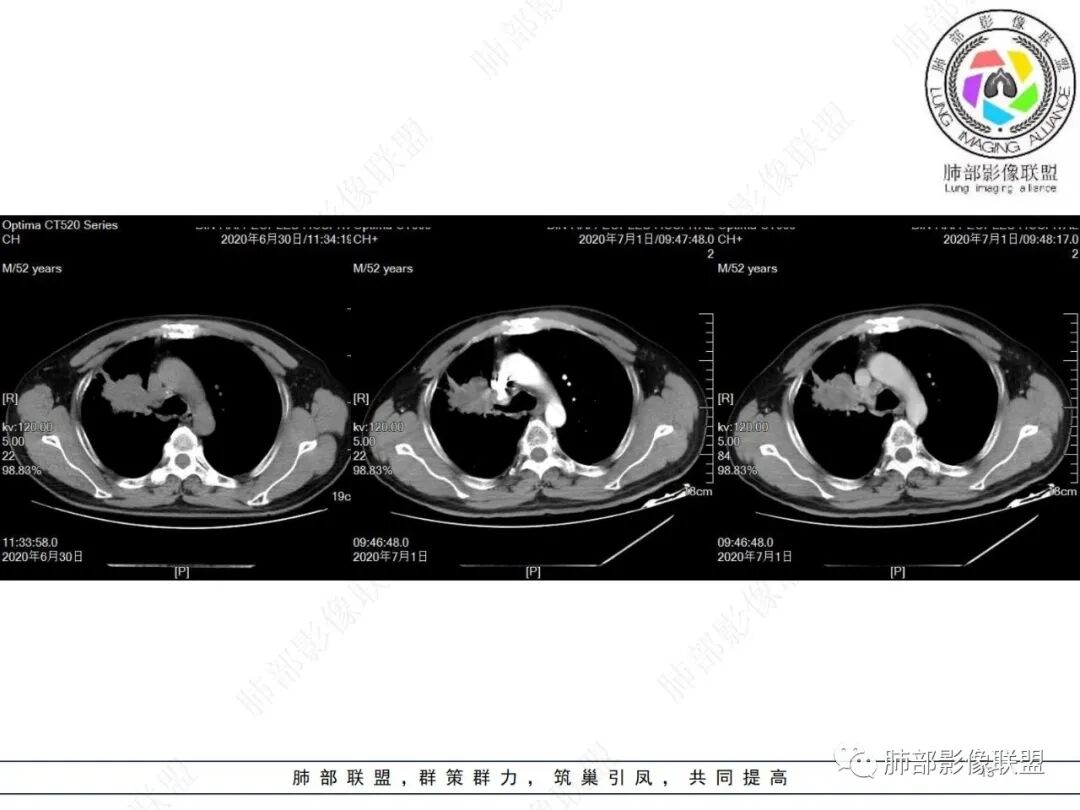

右肺上叶不规则形软组织密度肿块影,边缘见分叶,毛刺,病灶呈宽基底与胸膜相连,病灶内见坏死,增强扫描呈不均匀性强化,右肺上叶支气管截断,纵隔内见肿大淋巴结,肿瘤标志物增高,考虑鳞癌可能,鉴别小细胞癌,腺癌。

老年人,右肺上叶肺不张伴阻塞性炎症,右肺上叶支气管闭塞,增强病灶强化不均匀,可见边缘不清晰的坏死,纵膈淋巴结增大,考虑中央型肺癌,鳞癌可能性大。

右肺上叶不规则肿块,分叶、毛刺,上叶支气管截断,断端圆钝,不均匀强化,其内空泡及坏死,坏死边界不清,考虑腺癌或腺鳞癌,鉴别鳞癌

除了年龄,吸烟,湖泊样坏死符合鳞癌,其他都不符合,支气管截断,不在肿块中央,远处也没有明显阻塞样改变,更像爬行后截断,肿瘤标志物CEA高得厉害,其他鳞癌标志物并不高。这种坏死,低分化腺癌一样常见,强化远端也有强化,不符合鳞癌,所以我考虑低分化腺癌(伴或不伴有神经内分泌分化)或者肉瘤样癌。

不符合鳞癌有四点:1,截断的支气管不在肿块中央,而是外朝内爬行(肿块外缘大于近端)2、支气管截断在前段,前段远端没有阻塞性改变。3、鳞癌是近端强化,远端为阻塞性的不强化粘液栓或明显强化的不张肺组织,这个是中间坏死,周围强化的肿瘤组织。4、肿瘤标志物CEA增高太明显,鳞癌标志物不高。

化疗后